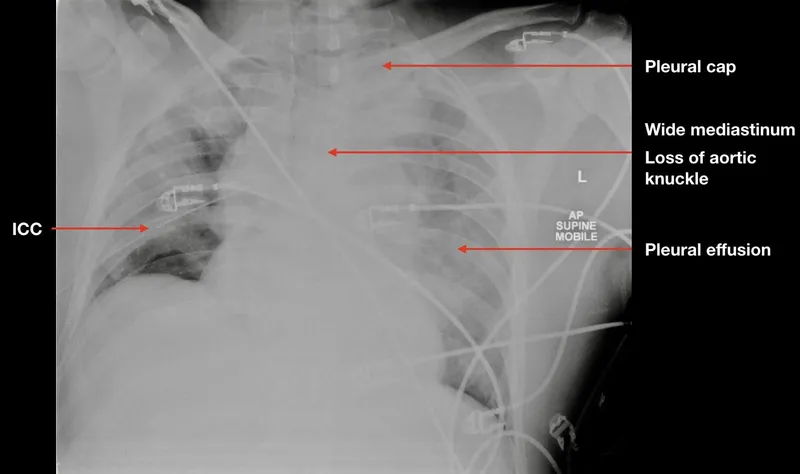

- Aortic Injury: Deceleration injury classic. Look for widened mediastinum (>8cm) on CXR, left hemothorax. Gold standard: CT Angio. Manage BP & HR (Labetalol) before surgical/endovascular repair.

⭐ The most common site of traumatic aortic rupture is the aortic isthmus, just distal to the left subclavian artery.